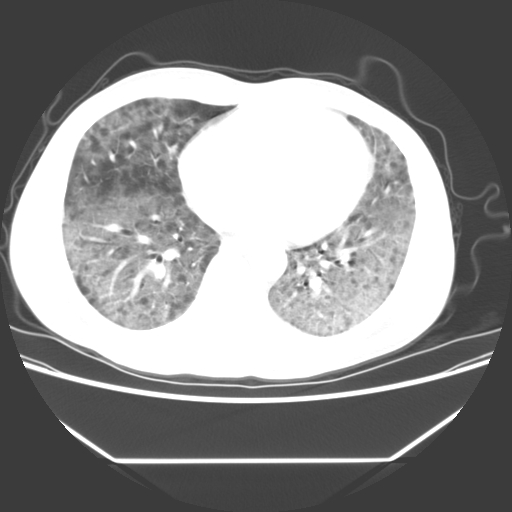

病人55岁,咳嗽,胸闷

忘了传病史了,病人55岁,咳嗽,胸闷

两肺部呈“毛玻璃”状改变,原因待查考虑感染性病变

病人是否发烧,两肺“磨玻璃”影,其间见空气支气管征和碎路石征。考虑肺泡蛋白沉着症。

两肺广泛对称磨玻璃样影,密度不均,考虑机遇性肺部感染。

双肺弥漫磨玻璃样病变,病史很重要。有感冒或发烧史,甲流不除外。无发烧可考虑肺泡蛋白沉积,但肺泡蛋白沉积边缘往往较清晰,与正常肺组织分界清晰

两肺弥漫间质性病变,考虑肺泡蛋白沉着症。建议进一步检查。